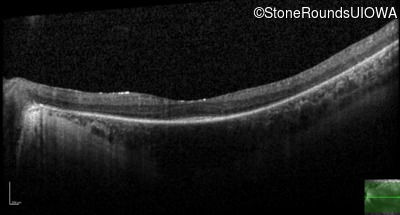

Optical Coherence Tomography - Right - 20/80 -2

Exemplar / OCT Stack

OCT Stack

Optical Coherence Tomography - Left - 20/80 -2